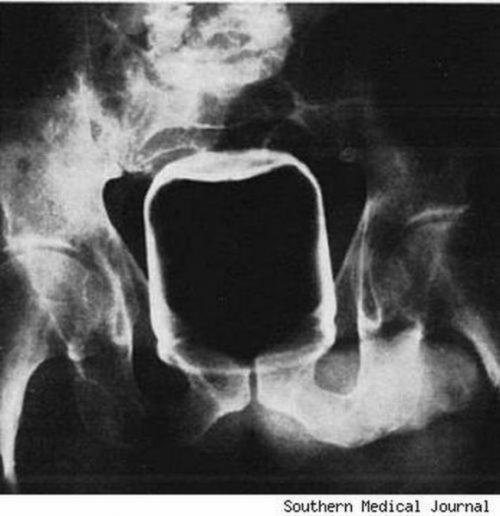

Банка из-под арахисового масла